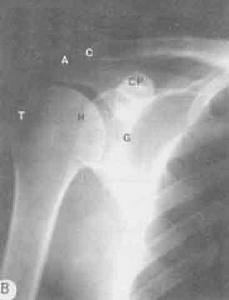

肩關節正位,患者直立於攝片架前,背靠暗盒。暗盒上緣超出肩部軟組織,肩胛骨喙突對暗盒中線,身體健側約向前轉35度,使肩胛骨與暗盒平行並緊帖。被檢側手臂與軀幹分開,稍向內旋,手部靠腰,肩關節放於暗盒中心。

中心線:對準肩關節中心,與暗盒垂直。